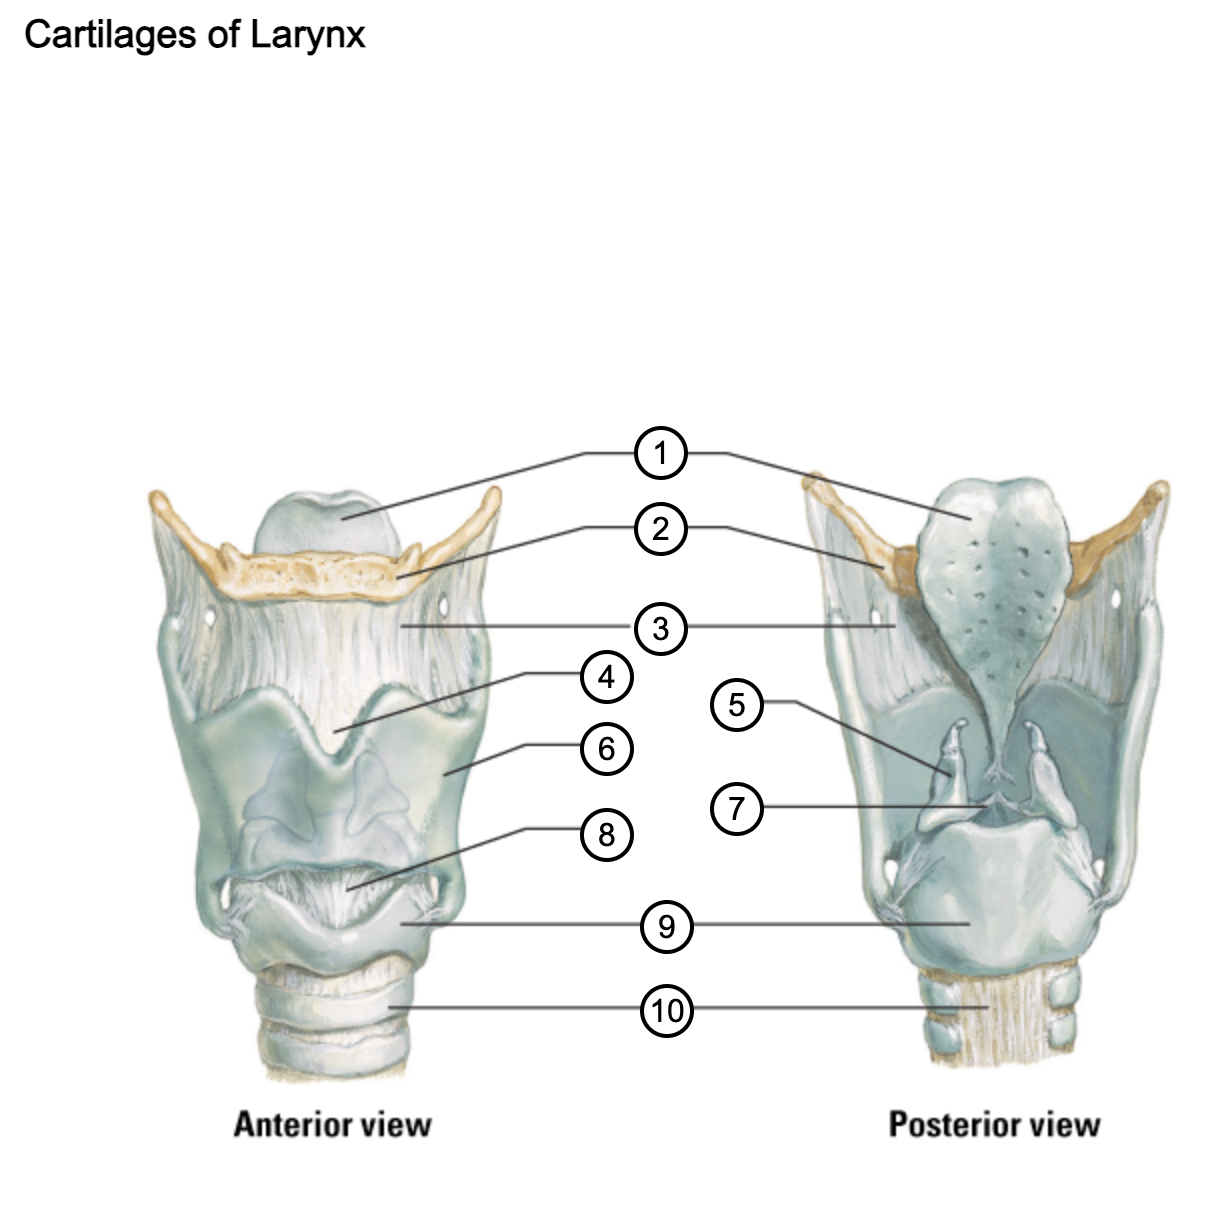

1

epiglottis

2

hyoid bone

3

thyrohyoid membrane

4

superior thyroid notch

5

arytenoid cartilage

6

lamina of thyroid cartilage

7

vocal ligament

8

median cricothyroid ligament

9

cricoid cartilage

10

trachea